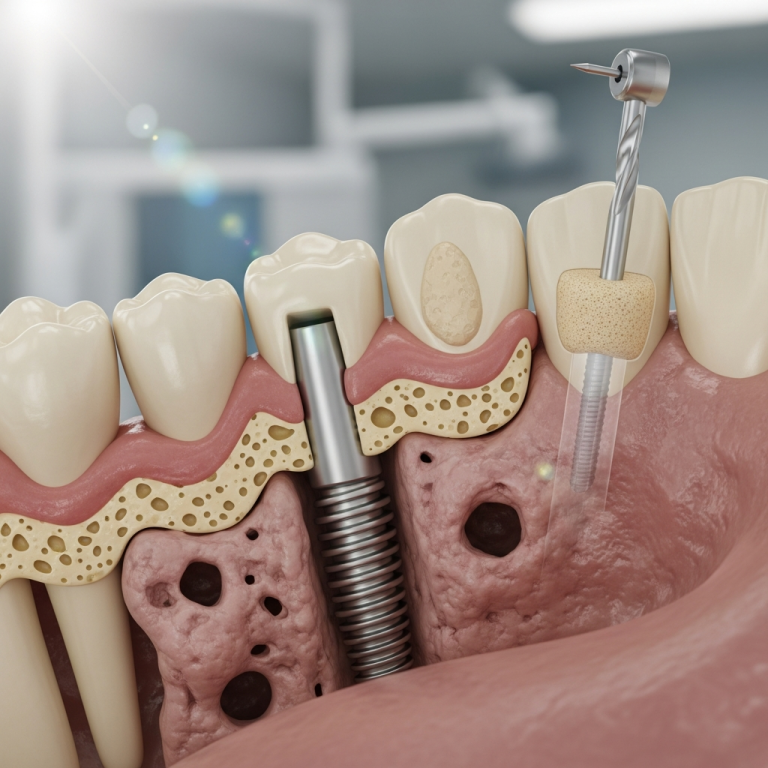

Implanturile bicorticale monobloc sunt structuri din titan cu un singur corp, fără șurub de protezare. Ele sunt proiectate să se ancoreze simultan în cortexul osos vestibular și palatal/lingual, oferind stabilitate primară imediată. Această ancorare dublă este posibilă în zonele cu os bazal dens, cum ar fi regiunea sinusală sau pterigo-maxilară.

Tehnica de inserție și ancorare bicorticală

Succesul depinde de o tehnică chirurgicală precisă. Implantul este inserat la un unghi strategic pentru a angaja ambele tăblii osoase corticale. Aceasta asigură o fixare mecanică robustă, reducând micro-miscarea și promovând o vindecare fără complicații. Planificarea 3D preoperatorie este esențială pentru a identifica traseul optim și a evita structurile vitale.

Implanturile bicorticale sunt indicate în primul rând pentru pacienții cu atrofie osoasă severă la nivelul maxilarului posterior, unde implanturile clasice necesită grefă prealabilă. Spre deosebire de osteointegrarea tradițională (care necesită 3-6 luni de vindecare), abordarea bazală se bazează pe ancorarea mecanică în osul cortical dens, cu recuperare funcțională în câteva zile sau săptămâni. Implanturile clasice rămân însă standardul de aur pentru zonele cu volum osos suficient.